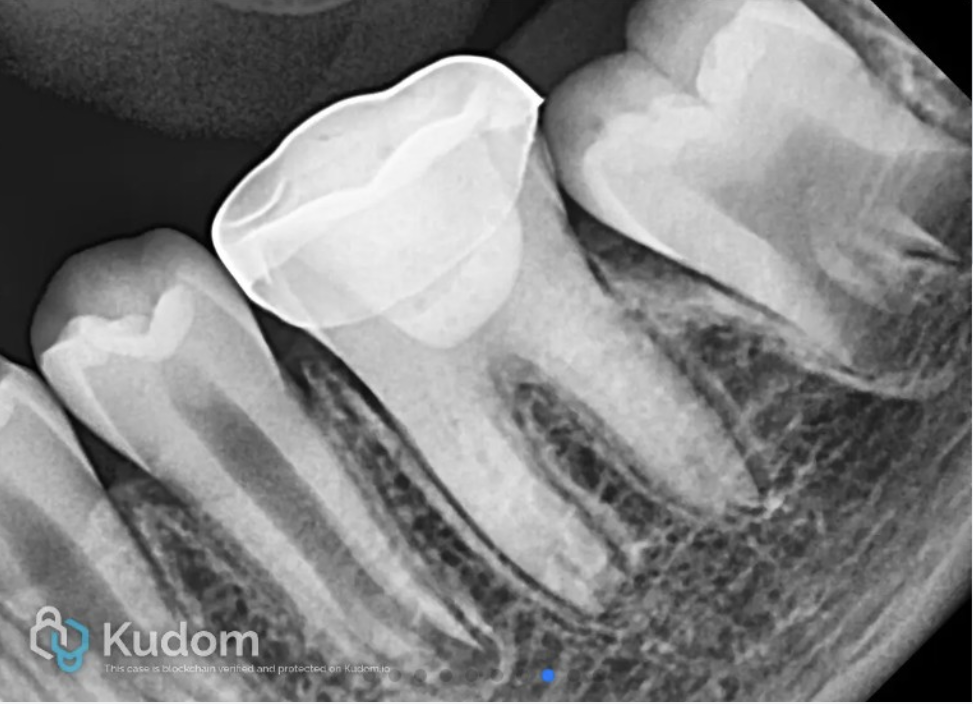

Radiograph of 36 showing Biodentine® in canals and access closed with composite.